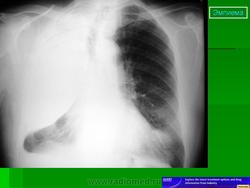

Левосторонний паракостальный осумкованный плеврит.

Правосторонний паракостальный осумкованный плеврит.